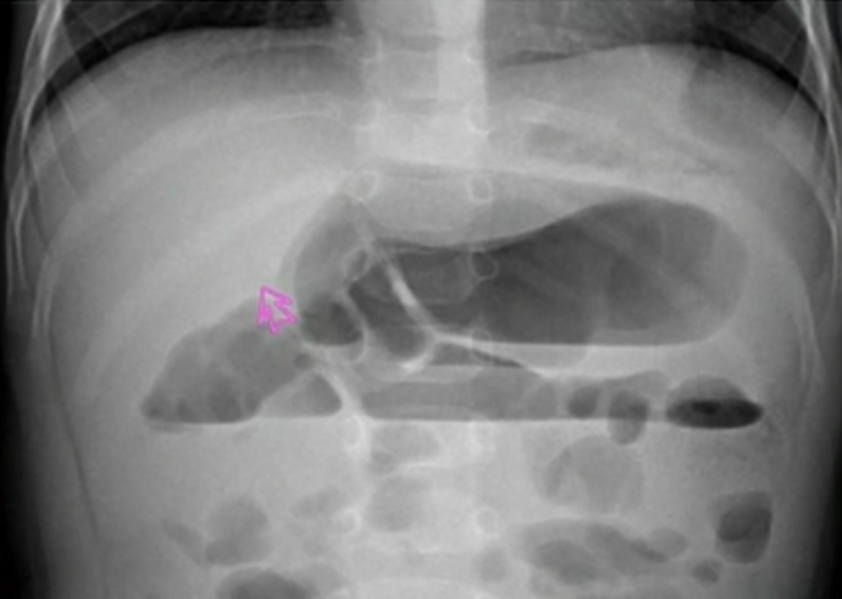

- 胆囊结石:正常胆囊里面液体应该和胃内部类似

- 肝门内胆囊里有高密度影

- 肾结石

- 在集合系统, 空腔附近